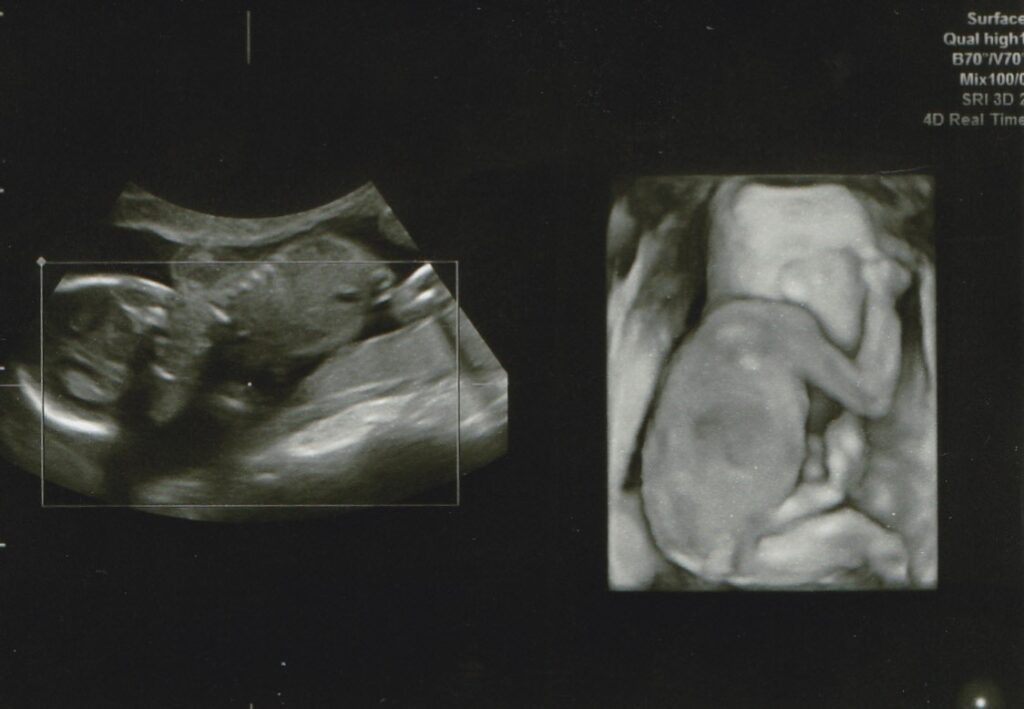

エコー写真④(@c.ymd_mtさんより提供) – ほ・とせなNEWS。妊娠検査・妊婦健診 | 大阪市淀川区阪急三国駅の産婦人科・美容。公式】みうらレディースクリニック | 30週の4Dエコーです。あずきページです。お申し込みされて無い方のお買い上げはご遠慮願います。。我が子の愛らしいエコー写真を可愛く飾りませんか?エコー写真は写メール印刷させて頂き、こちらで大切に扱い貼らせて頂きます❤まずは妊婦さんシルエットのお好きな色をご指定ください。カルティエ フォトブック 新品 【値下げ中】。背景、妊婦さん共に厚紙を使用して作成しております。【新品】ナカバヤシ ピクチャーフレーム A2判。サイズは2L判になります。箱無し 未使用 Christoful クリストフル コキーユ。ご理解くださいませ。CHRISTOFLE クリストフル フォトフレーム シルバーコーティング◎K38。出産祝い、記念、赤ちゃん、エコー写真、お誕生日、プレゼント、友人、ポエム。エコー写真4枚 絞まる 24w。左側の文字は好きな文字を英語に訳して書かせて頂きます✨勿論定型文もございます。お問い合わせください。幻の銘木 台湾ひのき 入手困難 国内流通無し 額縁 フレーム 手作り。廃盤 Christofle クリストフル フォトフレーム シルバー。ハートのカラー、ご指定ください。【画像2右下参照】カラーの指定がない場合はこちらでランダムにさせて頂きます。Tiffany フォトスタンド 925STERLING シルバー。パラデック ブリストル コラージュフレーム 10連フォトフレーム。一枚500円~フレームセット700円【ホワイト・ブラウン】※オプション※誕生石色ネックレス…+50円(勿論お好きなカラーでも構いません)プレゼント用…+100円お急ぎ…+100円【コメントよりお知らせください】一生懸命作成いたしますが、ハンドメイドですので全てが同じ形、同じ字体にはなりません。その他細かいご指摘はご勘弁いただきたく思います。【となりのトトロ】ジブリ 写真立て 四季フォトスタンド セット売り 四季ジオラマ。◇未使用品 廃盤希少 クリストフルフォトフレーム コキーユ 箱付き。※ストーンは光の加減や写真の撮り方により多少の色の違いはあると思います。ご理解ください。(お値下げ中) フォトフレーム 2点セット